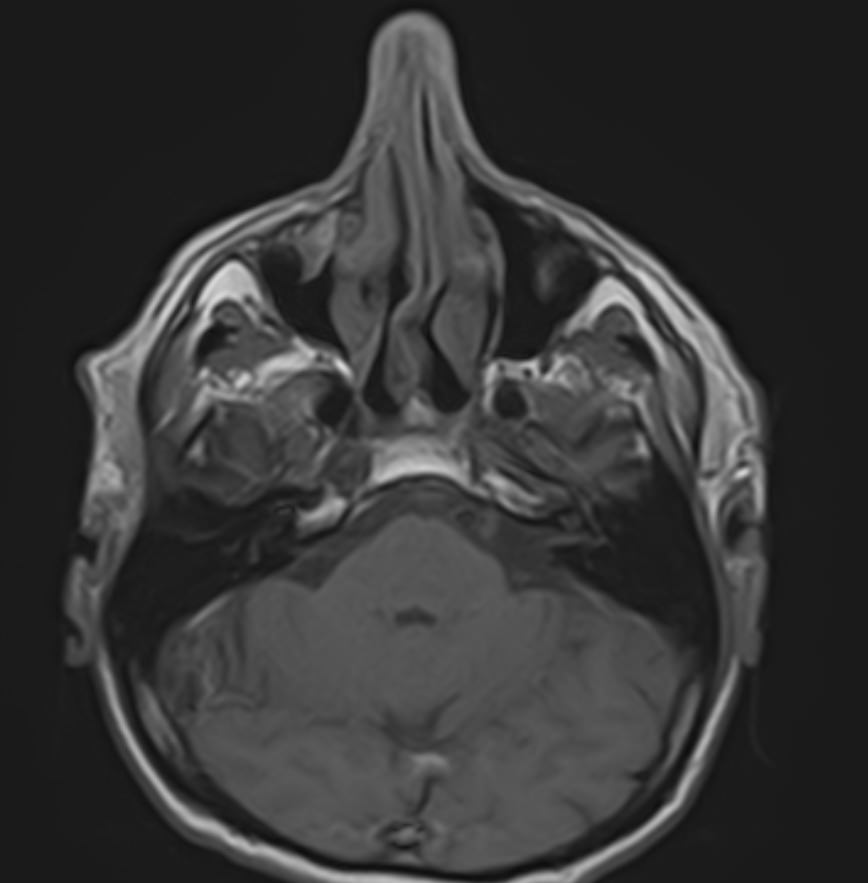

Магнитно-резонансная томография (МРТ) мягких тканей лица – это неинвазивное диагностическое исследование, которое использует магнитное поле и радиоволны для получения детализированных изображений структур мягких тканей в области лица. МРТ мягких тканей лица позволяет визуализировать мышцы, жир, нервы, сосуды и другие мягкотканные структуры, что помогает в диагностике различных заболеваний и патологий, таких как:

Перед проведением МРТ мягких тканей лица обычно требуется консультация врача, который определит необходимость и целесообразность исследования, а также даст рекомендации по подготовке. В некоторых случаях может понадобиться введение контрастного вещества для улучшения визуализации структур и выявления патологий.